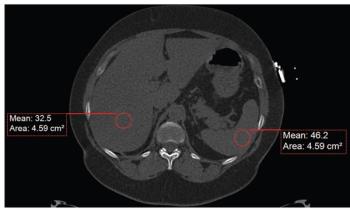

Case History: 60-year-old female with shortness of breath worsening with exertion and fatigue.